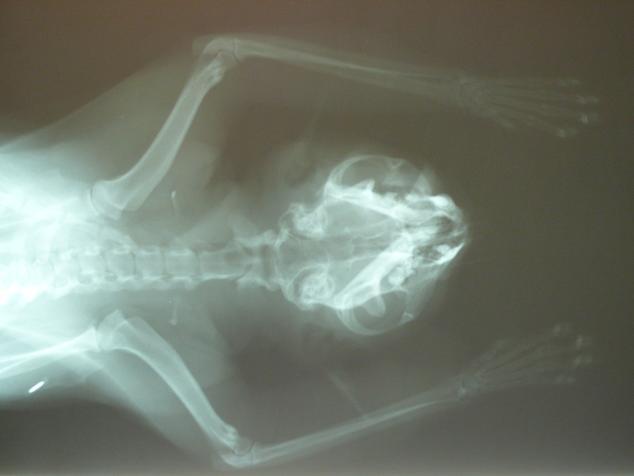

沒想到,我看到鐵沙掌的兩隻前腳上肢,不僅傷口腫大,遭利刃割傷,傷口平整,血似乎是乾掉了.於是我趕緊到附近醫院借了誘捕籠抓牠.還好牠沒跑遠,讓我順利抓到.我立即帶牠去長沁就醫.張醫師先為牠照了X光,確認腳沒斷,便趕緊清創.

由於傷口面積都是橫切,而且傷口很大,因此無法動手術,只能等到傷口慢慢復原.也因為鐵沙掌會緊張,所以兩三天將牠麻醉後換藥.